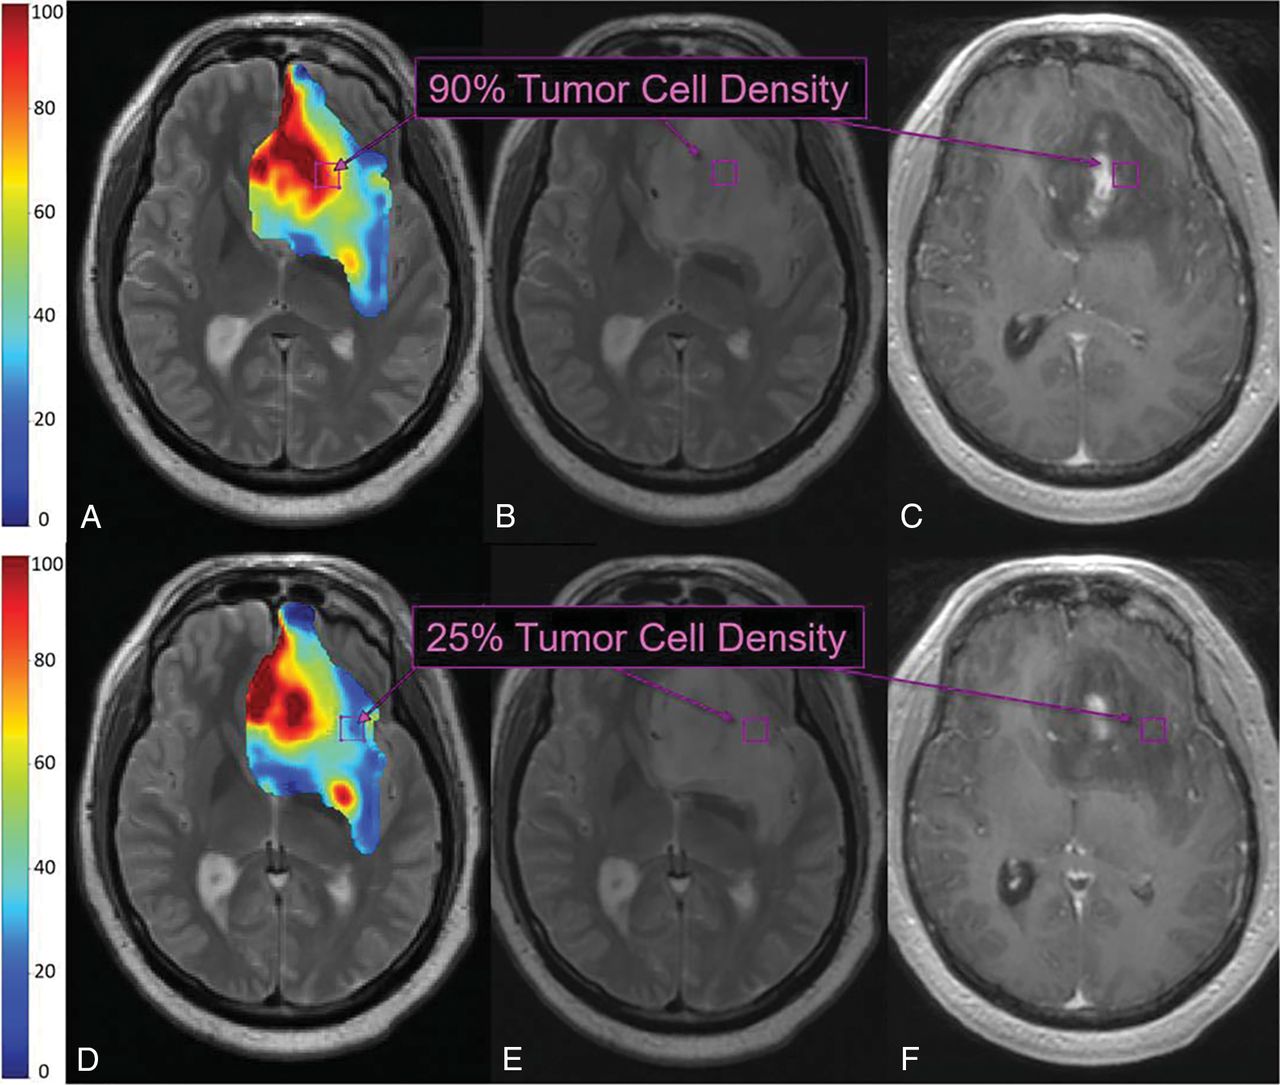

On the basis of the results from univariate analysis and individual scatterplots, we prioritized rCBV for training of TL and constrained knowledge transfer from patients with an arbitrary threshold for correlation between rCBV and TCD (r ≥ 0.10). By means of LOOCV, the TL model with rCBV as the sole model predictor improved the correlation between predicted-versus-actual TCD (r = 0.53, P < .001, n = 82), compared with the generalized OMFA model, which also used rCBV as the sole predictor (r = 0.27 using LOOCV) (Table 2). We then quantified incremental gains from adding other MR imaging contrasts to the rCBV-based TL model. As shown in Table 2, individualized transfer learning models consistently improved correlation coefficients and mean error rates compared with corresponding generalized OMFA models. Figure 1 shows the scatterplots for actual-versus-predicted TCD using the highest performing TL model, which incorporated rCBV, T1 + C, FA, and MD as model predictors. After LOOCV, this model achieved a Pearson correlation of r = 0.88 (P < .001) across all samples (n = 82), which further increased among nonenhancing T2/FLAIR samples alone (r = 0.94, P < .001, n = 33). By comparison, the generalized OMFA approach, using the same model predictors, achieved much lower correlation coefficients for all samples (r = 0.39, n = 82) and nonenhancing samples alone (r = 0.09, n = 33). As shown in Fig 2, the TL model can be used to generate color overlay maps of predicted TCD that correspond with actual TCD from spatially matched biopsies throughout different nonenhancing regions in the same GBM tumor.

TL maps and multiple biopsies in a 71-year-old patient with primary GBM. TL-based color map overlay on a T2-weighted image (A) shows predicted regional TCD ranging from 0% to 100% (blue to red) throughout the segmented tumor region (based on the T2-weighted signal abnormality). Histologic analysis of the top biopsy (purple boxes B and C) yielded 90% TCD, corresponding to red regions of high TL-predicted TCD (purple box, A). TL-based color map (D) from a more caudal T2-weighted slice shows blue regions of low TL-predicted TCD (blue/green, purple box), corresponding to 25% TCD on histologic analysis of the bottom biopsy (purple boxes, E and F).